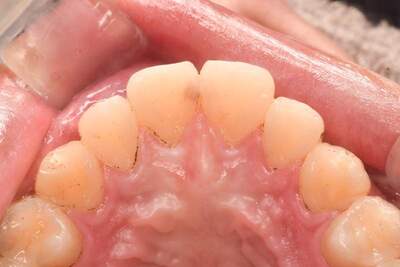

症例② CR

治療前

治療後

年齢 30代・男性

主訴 右上1番

治療内容 右上1番CR

治療費 右上1番CR:約1.500円(保険診療3割負担)

(2022年7月現在)

治療期間 1日

リスク・副作用 麻酔がきれた後に痛みがでる可能性がある。

治療方針 口蓋側近心から虫歯をとり、CR充填を行う。

特記事項 治療後痛みはでていない。

担当者所見 唇側には広がっていなかったので、審美的な問題はおきないと考えられる。

症例③ CR

年齢 40代・女性

主訴 前歯の黒いのが気になる

治療内容 右上2番、左上2番

治療費 約2.200円(保険診療3割負担)

(2022年6月現在)

治療方針 両側共に頬側遠心から隣接にかけて、虫歯をとって、CRをつめる。

特記事項 虫歯になりやすい方なので、歯間の清掃指導を行った。

担当者所見 虫歯が歯髄近くまで広がっており、しみるのが続く場合は抜髄の可能性がある。